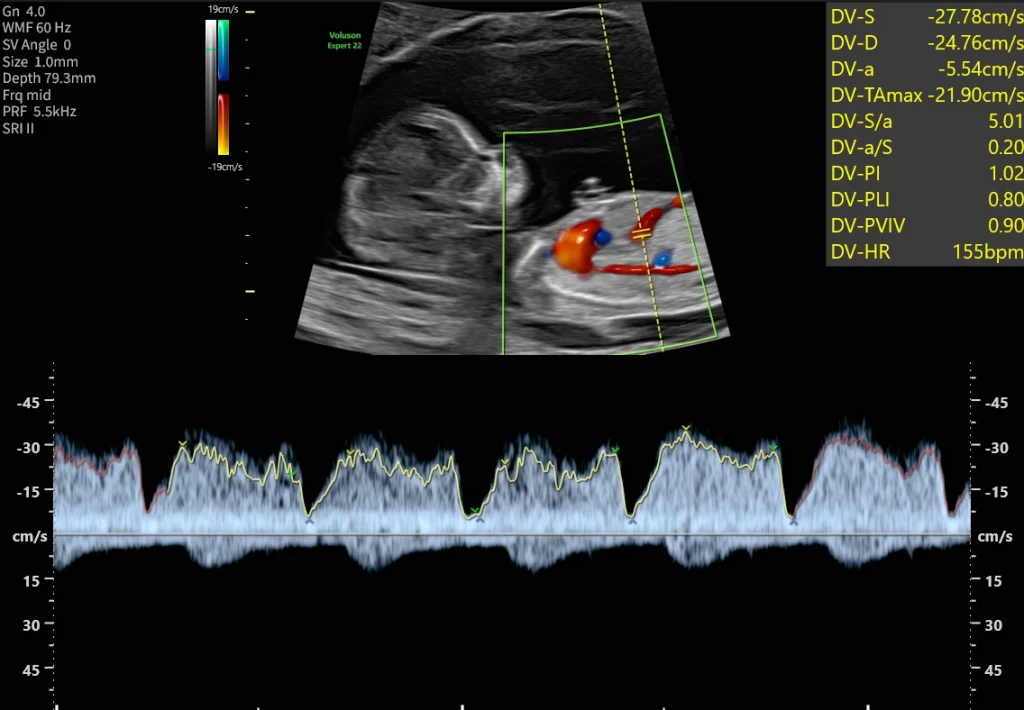

Zusätzliche Kriterien sind die Messung des kindlichen Nasenbeins, Beurteilung des Blutflusses über den Herzklappen und Messung des venösen Blutflusses zum kindlichen Herzen hin. Parallel dazu können aus einer mütterlichen Blutprobe zwei Schwangerschaftshormone (freies ß-HCG und PAPP-A) analysiert werden. Besonders hohe oder niedrige Konzentrationen sind als Risiko für das mögliche Vorliegen von Chromosomenveränderungen und einer Reihe weiterer Erkrankungen zu werten. Aus den biochemischen Ergebnissen, den Ultraschalldaten und Ihren persönlichen Daten wird ein individuelles Risiko für Chromosomenstörungen in der vorliegenden Schwangerschaft errechnet.